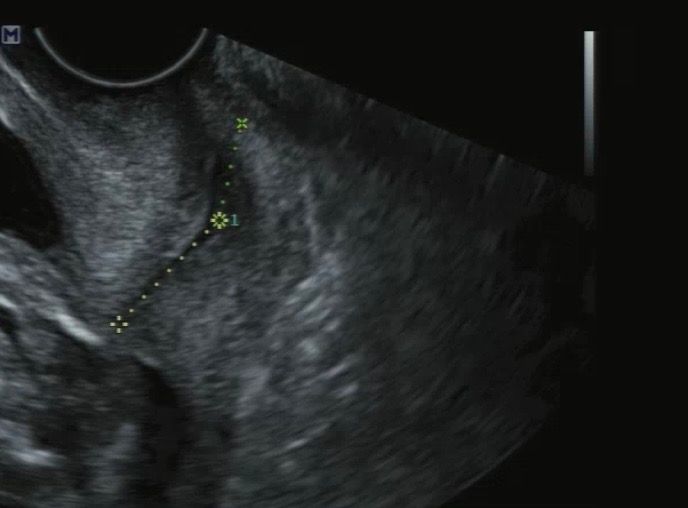

자궁경부길이 관련 사진입니다. 많은 답변 부탁드려요.

각자 다른 원장님께서 측정해주신 자궁경부 길이입니다.

첫번째사진은 끝쪽까지 길이를 재주셨는데

두번째사진은 중간까지 길이만 재주셔서요..!

왜 다를까요?????